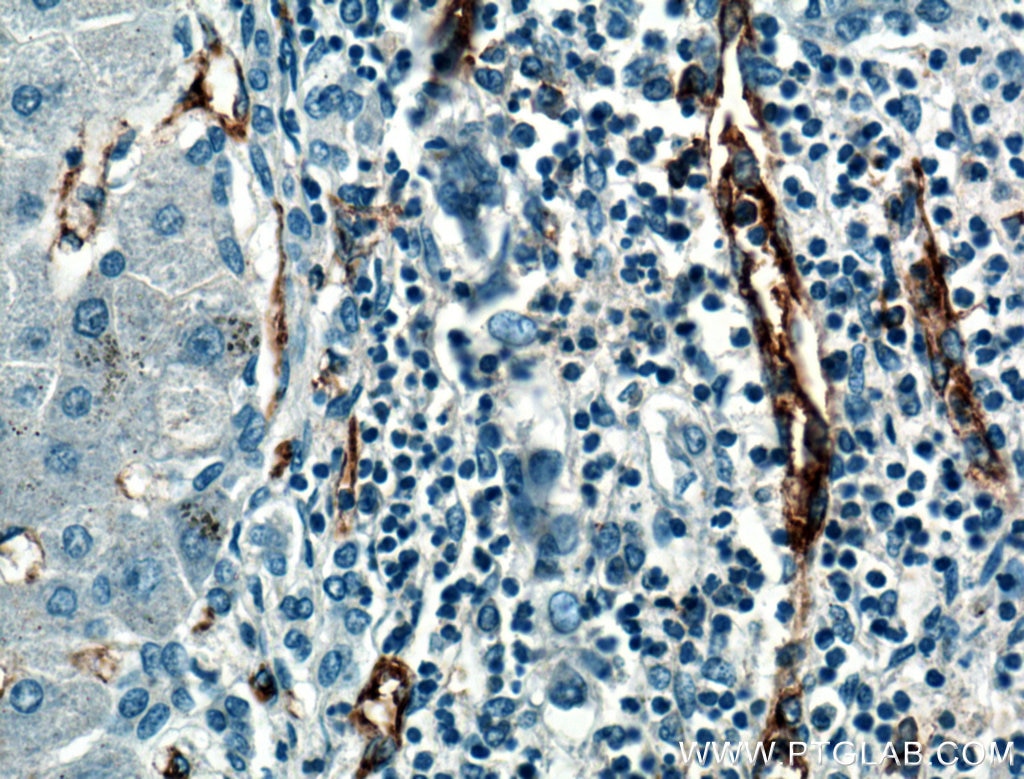

PathPlus PECAM-1 CD31 Antibody LS-B4737 is a pathologist validated IHC antibody Rabbit anti-Mouse PECAM-1 CD31. Tested on 20 paraffin-embedded human tissues. CD31PECAM-1 was detected in immersion fixed frozen sections of mouse embryo 14 dpc using Goat Anti-MouseRat CD31PECAM-1 Antigen Affinity-purified Polyclonal Antibody Catalog AF3628 at 10 µgmL for 1 hour at room temperature followed by incubation with the Anti-Goat IgG VisUCyte HRP Polymer Antibody Catalog VC004.

Tissue was stained using DAB brown and counterstained with. CD31 PECAM-1 is a transmembrane glycoprotein member of the immunoglobulin supergene family of adhesion molecules. CD31 is expressed by stem cells of the hematopoietic system and is primarily.